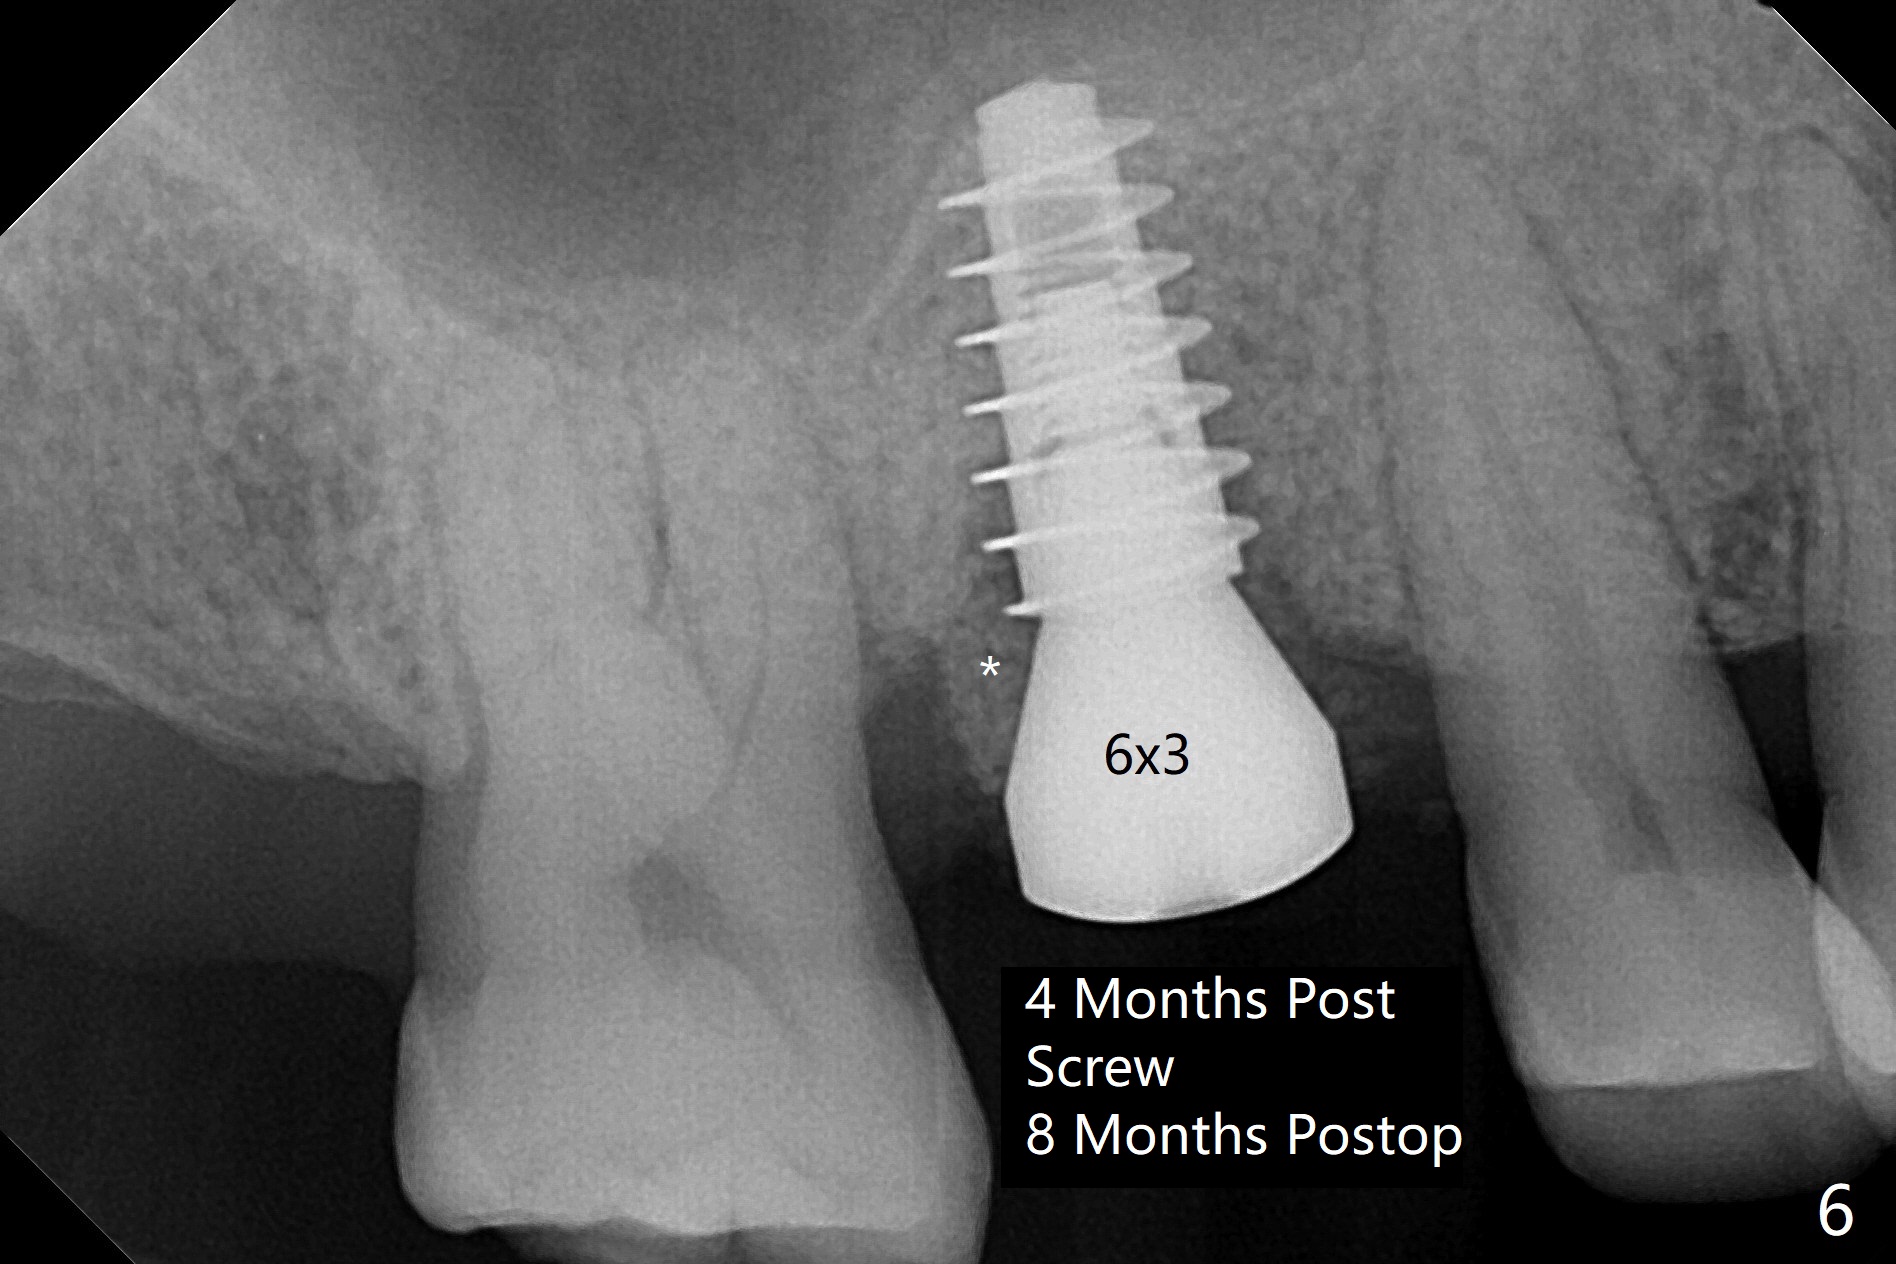

60岁男以前就害怕牙科治疗,一年前做一侧肾上腺切除,现在更紧张,不过挺配合。右上6手机切断拔除,虽然近中颊侧牙槽窝破坏厉害,中隔还很大(图一:S),利用导板顺利完成钻洞和提升术(图二:*)。植入正式植体后,放置第一轮粘性骨粉,至植体水平(确保植体深部周围没有缺失)而不影响基台置入,近中有不足之处(图三:*),第二轮骨粉补充(图四),最后覆盖PRF膜,临时牙冠固定。The crown/abutment/implant are found to have mild mobility 4.5 months postop, as related to #19 infection. A healing screw is placed. One month later, the wound heals; the bone density in the sinus increases (Fig.5 *), while that coronal to the implant decreases (^).愈合帽放置4个月,伤口还没有完全愈合,翻瓣后发现远中螺纹表面肉芽组织覆盖,去除后者,第一螺纹暴露。放置愈合基台后,从颊侧往远中缺陷填入骨粉(图六:*),缝合,覆盖树脂敷料。